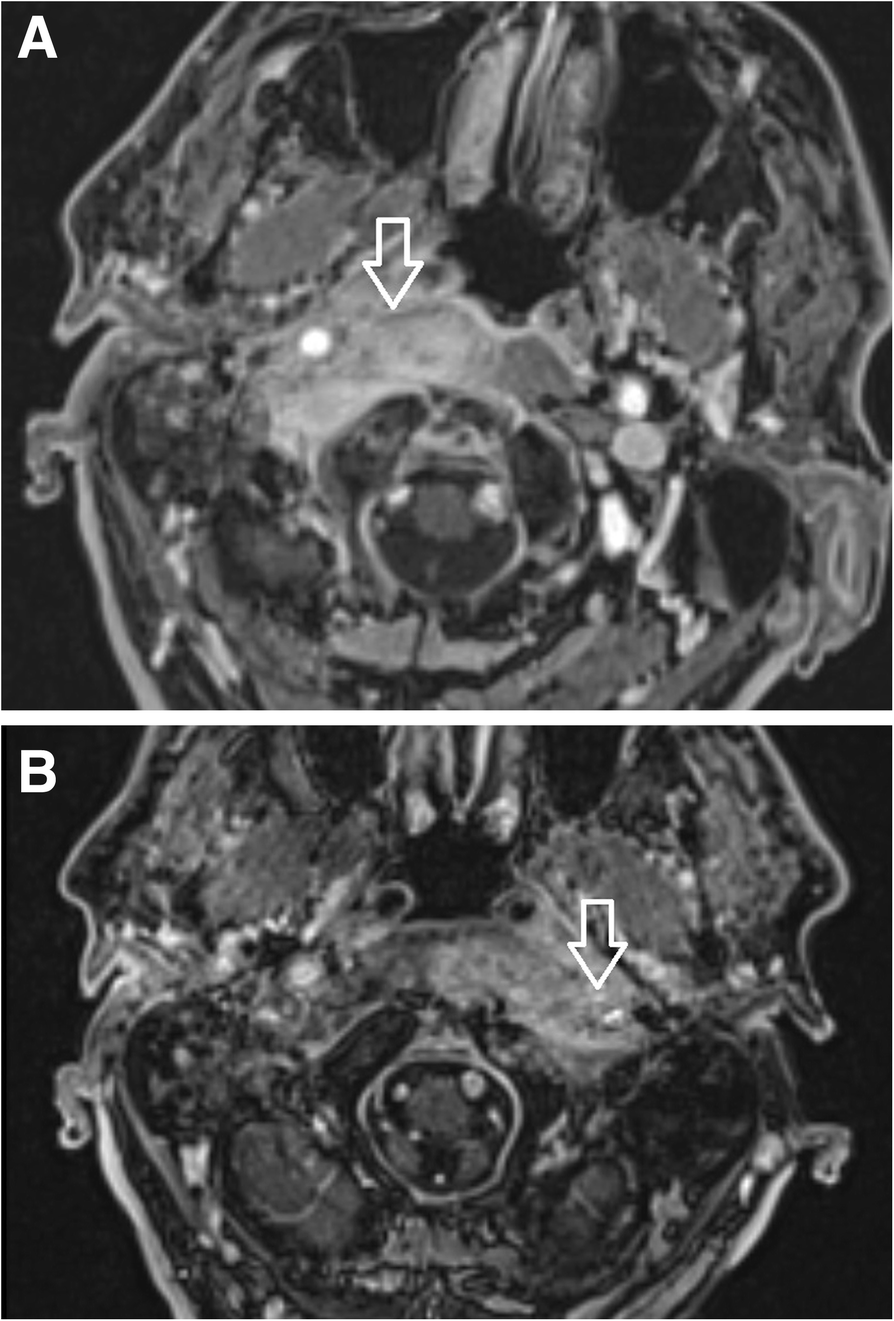

Fig. 12

a Patient 1, 2 months after the first clinical symptoms: MRI of the skull base. Contrast-enhanced axial T1-weighted spin-echo image with fat saturation. Inflammatory changes of the right side soft tissues beneath the skull base, musculus longus capitis and musculus rectus capitis anterior (arrow). The swelling extends to the midline; the infection originates from the right external auditory canal. b Patient No. 1, 4 months following the first clinical symptoms: MRI of the skull base of the same patient. Contrast-enhanced axial T1-weighted spin-echo image with fat saturation. After antibiotic treatment: ceftazidime, ciprofloxacin, clindamycin, Oxacyllin. Inflammatory changes of the soft tissues below the skull base progressed to the left side (arrow), musculus longus capitis and musculus rectus capitis anterior. The swelling affects the retropharyngeal and retrostyloid part of the parapharyngeal space in the midline and progresses to the left side